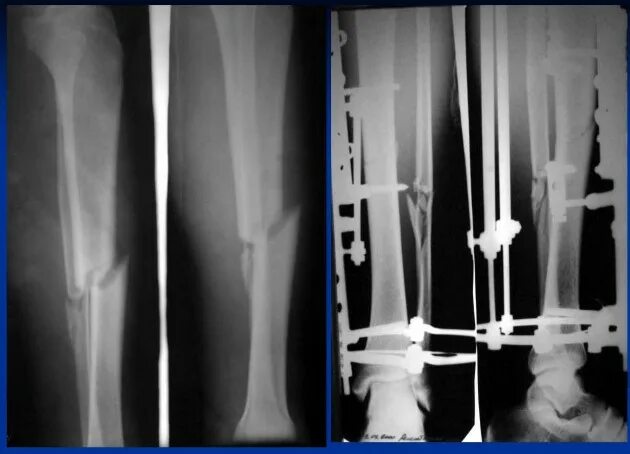

Операция на большую берцовую кость